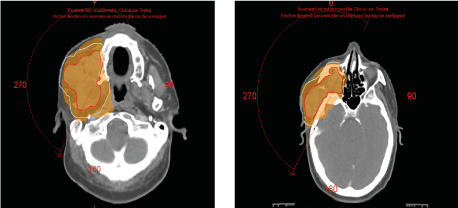

Most authors consider ameloblastoma to be radioresistant. Whereas in 1982 Reynolds wrote a major article on the effect of irradiation on ameloblastoma in which he discussed the basic principles of radiation therapy and concluded that radiotherapy has a place in locally advanced tumors or cases of surgery is refused [27]. A second important document is that of Atkinson in 1984, who published a series of 10 cases of ameloblastoma treated by radiotherapy, he concluded, based on his experience and the review of the literature that ameloblastomas are radiosensitive [28]. Since then, there are few published cases in the literature on the role of radiotherapy as a useful modality in the treatment of ameloblastomas [29-31]. Rastogi et al, published in 2006 a case of locally advanced ameloblastoma of the mandible which responded well to external radiotherapy, within recurrence after two years of follow-up [32]. Different forms of radiation therapy have been used successfully for non-surgical management of ameloblastomas especially in patients medically unstable for surgery. These include helical tomotherapy, image-guided radiation therapy, intensity-modulated radiation therapy, and proton beam therapy. During treatment planning, it is imperative to balance the efficacy of radiotherapy with the risks of developing future life-threatening malignant transformations. Our patient benefited from exclusive radiotherapy using the VMAT technique, at a dose of 60 Gy in 2 Gy per fraction (Figure 4).

Figure 4. Image showing dose distribution by VMAT